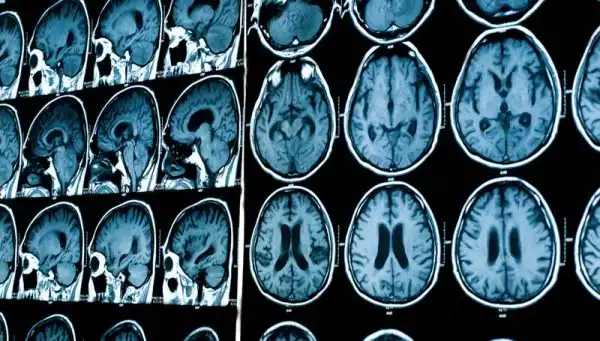

Есть такая область в мозгу, которая называется Парагиппокампальная извилина. Именно она отвечает за то, чтобы мы понимали какая информация к нам поступает из памяти, а какая происходит с нами сейчас наяву. И в те редкие ситуации, когда в этой части мозга происходит сбой, у нас и возникает ощущение дежавю.

Для простоты восприятия представьте себе наш мозг в виде большого, запруженного города. Когда всё в нём работает как надо, грузовичок с новой информацией едет самым очевидным коротким, а главное прямым путём из точки А в точку Б. От органов чувств к определённым структурам мозга, которые отвечают за обработку новой информации.

Но если на этом маршруте в мозгу по какой-то причине возникает «пробка», грузовичку приходится ехать в обход, объездным маршрутом. Как раз через те области мозга, в которых и хранится наша память. В частности — через правую височную долю. В итоге, когда сигнал, поплутав по извилистым улочкам мозга всё-таки добирается до цели, возникает сбой. На считаные секунды мозг перестаёт воспринимать информацию, которую привёз этот грузовичок как новую, только что увиденную глазом. А принимает её за нечто, поступившее из долговременной памяти. Именно поэтому нам и начинает казаться, что место в которое мы попали, или событие которое с нами происходит, нам уже знакомы.